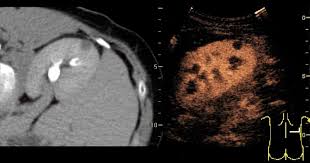

검사 결과 해석 방법

검사 결과는 영상의학과 전문의가 판독한 후, 진료과 주치의가 직접 설명합니다. 결과지에는 각 장기별 상태(정상/비정상), 이상 소견(결석, 종양, 낭종, 비대 등), 추후 검사 필요 여부 등이 기재됩니다.

결과에 따라 다음과 같은 조치가 이어질 수 있습니다.

- 정상 소견: 별도 조치 없이 추후 증상 모니터링

- 비정상 소견: CT/MRI 등 정밀 영상검사 필요

- 조직검사 필요: 간/췌장/신장 등 종양 의심 시